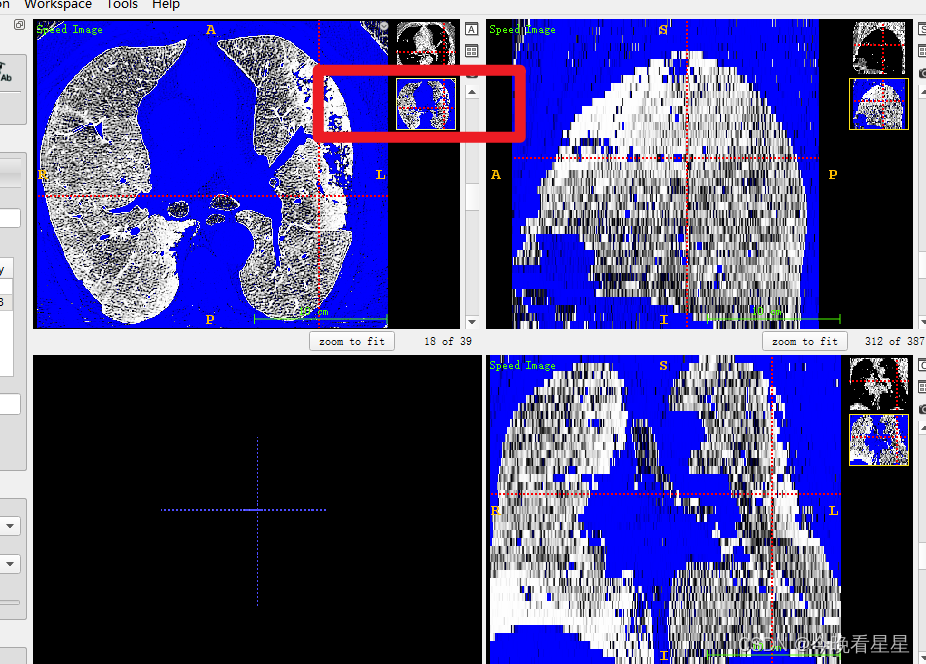

- 看第二个视图, 蓝色为丢弃区域,白色为选择的区域,进行CT阈值的调节,来选择想要的部分。参数调整完毕后,选择next进行下一步操作

- 在要扩散的区域选择点,进行自动扩散